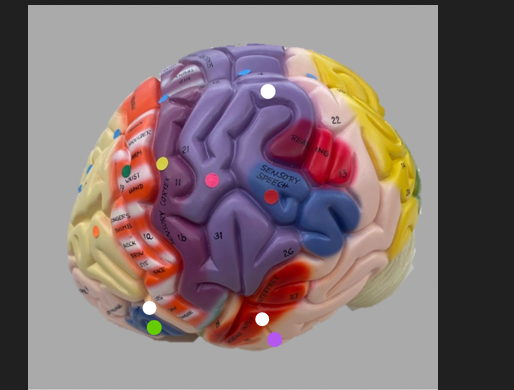

orange dot

frontal lobe

blue dot

longitudinal fissure

dark green dot

precentral gyrus

pink dot

postcentral gyrus

yellow dot

central sulcus

white dot

parietal lobe

light green dot

Broca’s Area

red dot

Wernicke’s Area

orange dot

occipital lobe

blue dot

parieto-occipital sulcus